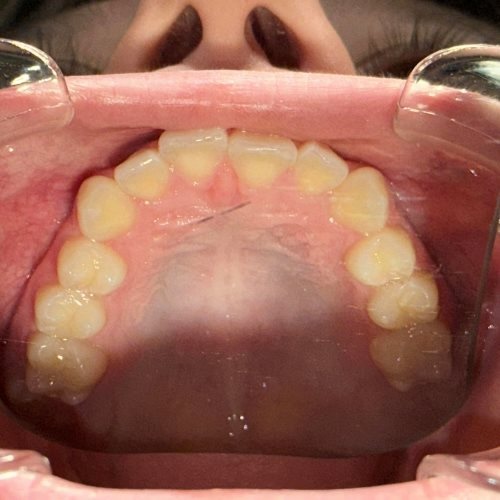

Każdy Pacjent ma inne potrzeby i inną wadę zgryzu, stąd zawsze powinna być przeprowadzana wstępna konsultacja, wyciski/skany, oraz pomiary by jak najlepiej zaplanować cały proces (i czas) leczenia, a przede wszystkim dobrać do potrzeb Pacjenta odpowiedni aparat ortodontyczny.

- wykonania precyzyjnego plan leczenia oraz indywidualnych skanów zębów Pacjenta skanerem wewnątrzustnym,

Aparat Invisalign® w większości przypadków nadaje się dla każdego Pacjenta, który ma zęby wyleczone oraz wyczyszczone z kamienia i osadu.